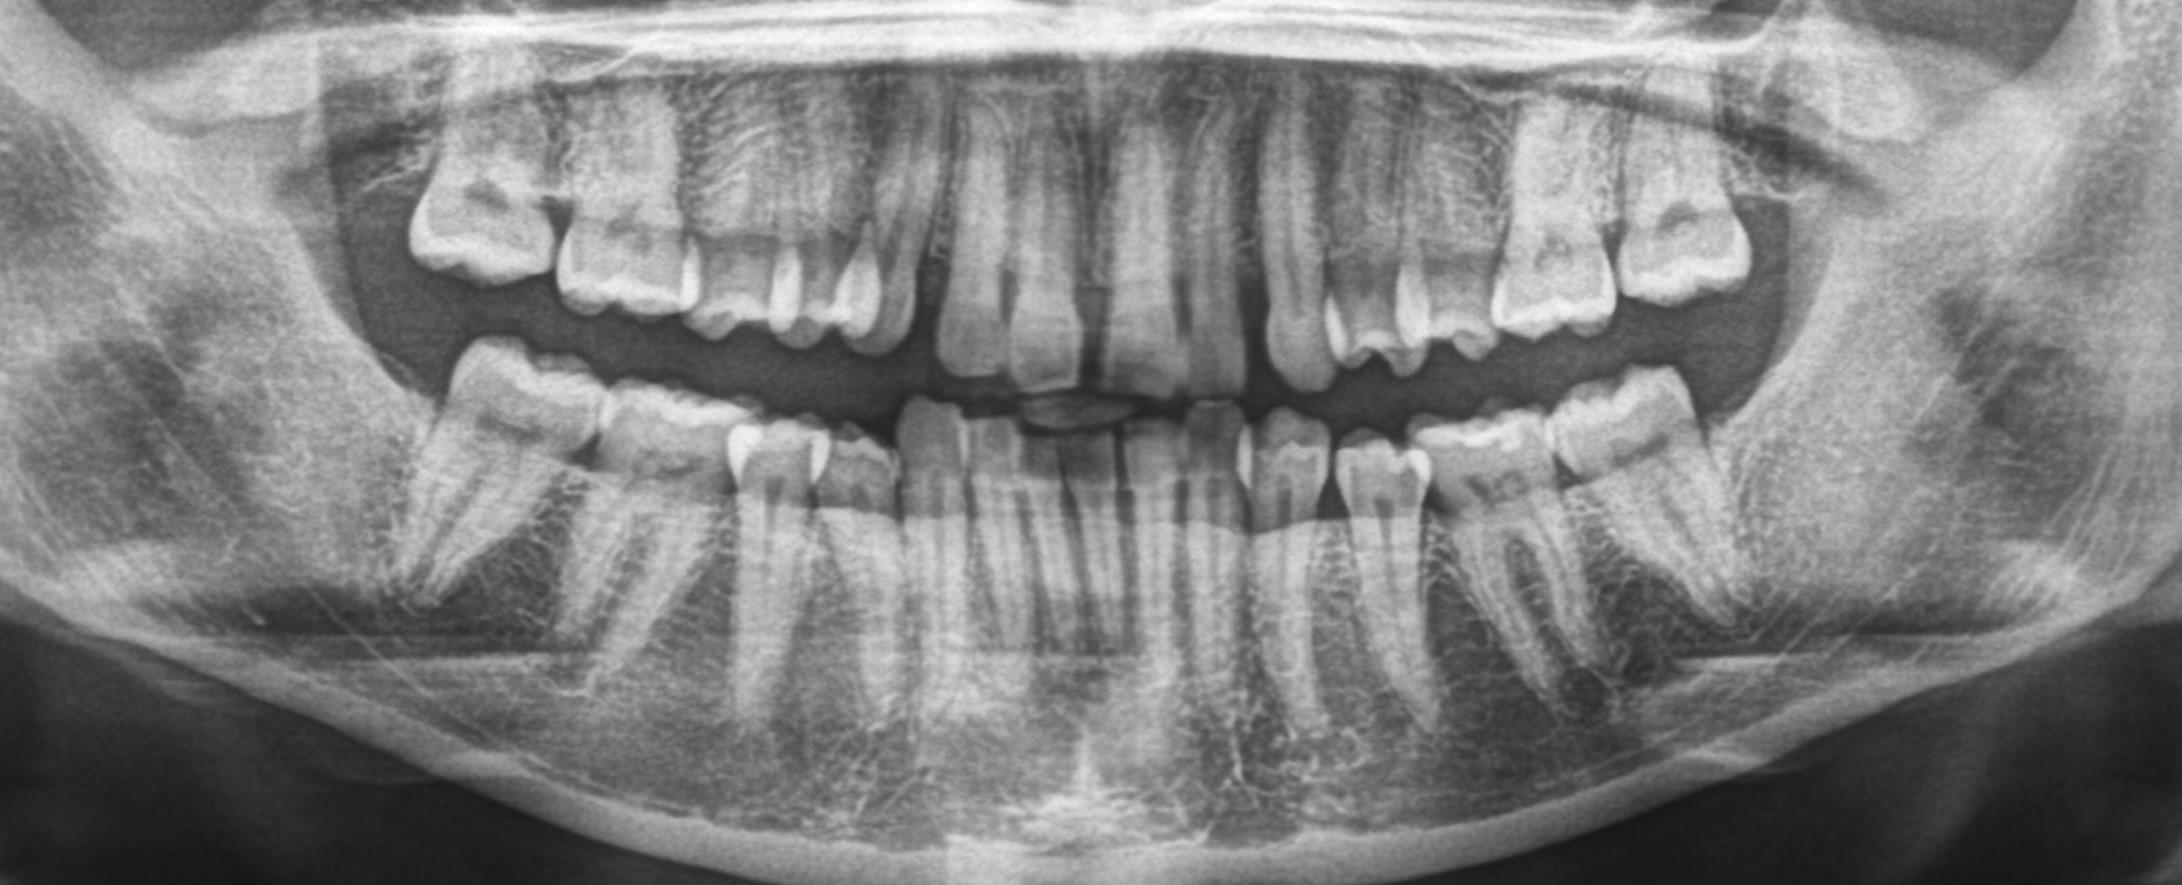

Discuss Dentistry » All Posts https://demo.discussdentistry.com/forums/forum/cosmetic-aesthetic-dentistry-2/feed/ Tue, 02 Sep 2025 00:41:25 +0000 https://bbpress.org/?v=2.6.11 en-US https://demo.discussdentistry.com/forums/topic/orthodontic-treatement-or-smile-redesigning/#post-26156 <![CDATA[Orthodontic treatement or smile redesigning]]> https://demo.discussdentistry.com/forums/topic/orthodontic-treatement-or-smile-redesigning/#post-26156 Mon, 12 Aug 2024 10:08:02 +0000 site_admin Dear all eminent orthodontists, Help required with this case.Female patient /Age…44 yrs / No relevant medical history

Patient came with a complaint of upper right central incisor drifting and  ” slightly coming outside.”  and it seems lower anteriors  have also tilted labially a little. This perhaps is due to gum recession and tartar accumulation.. The images shown below are after scaling.

What is the treatment?

Will orthodontic treatment work?  If yes can this case be done with aligners?

The local aligner company has suggested IPR of lower incisors and thereafter retroclination of U/L incisors. Is this possible or should I treatr the case with smile redesigning. The patient also wants other diastemas to be closed.  Hope to see a lot of responses and many thanks in advance for the same.